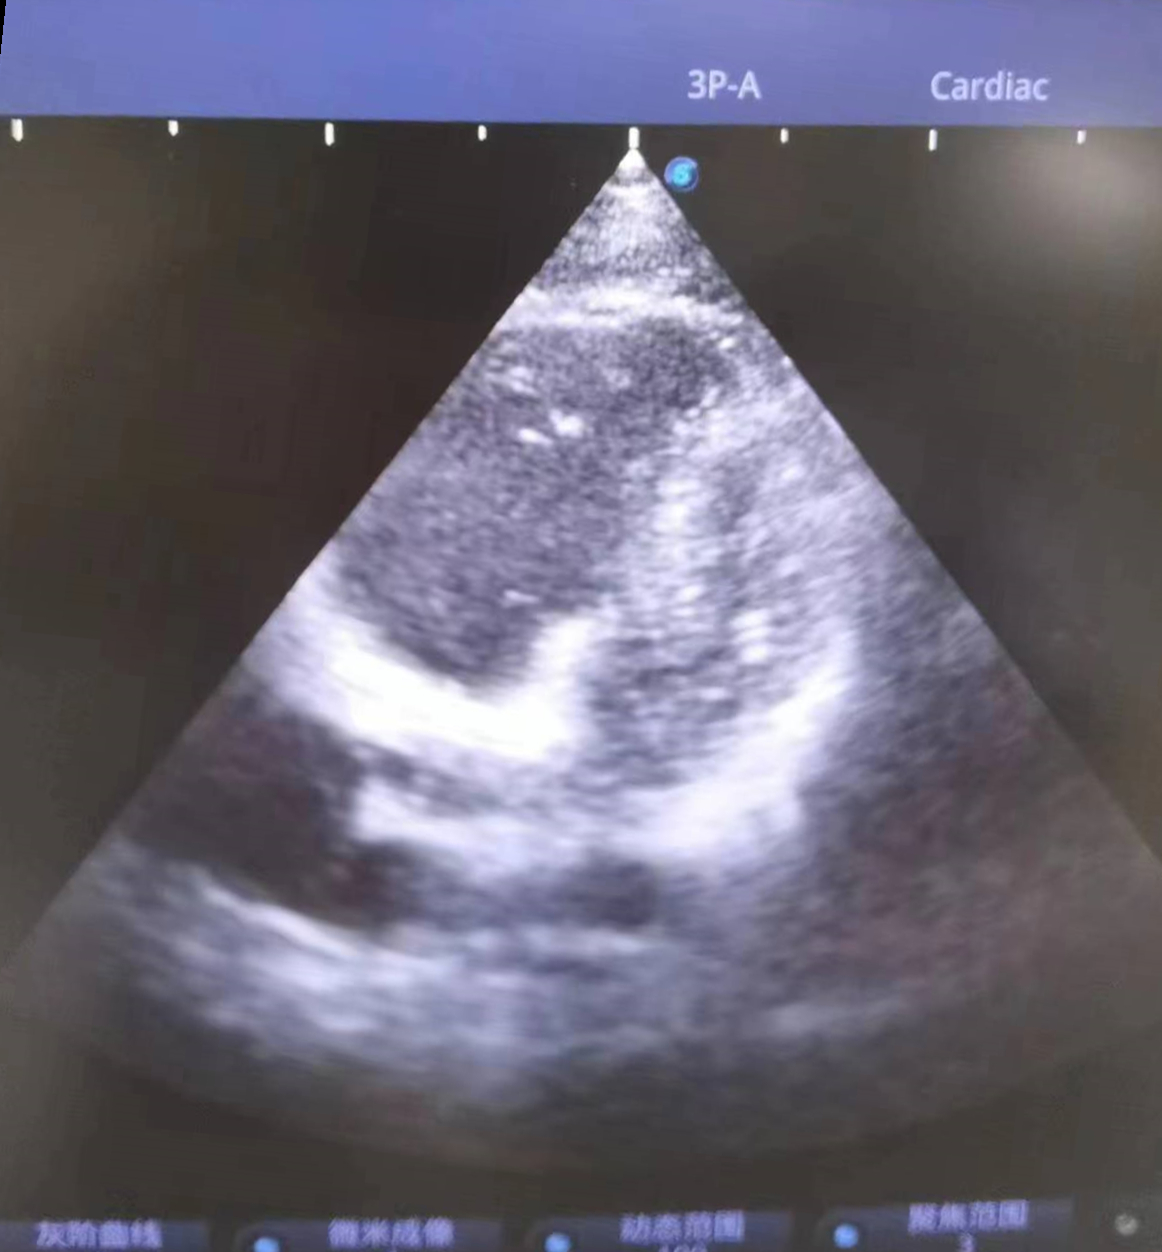

当天9点25分,小杨被送至急诊科,此时他面色苍白、呼吸困难、烦躁不安,无法配合治疗。急诊科医护紧急给予对症治疗,同时联系重症医学科(ICU)、心血管内科、超声影像科专家会诊。9点35分,小杨突然丧失意识,双侧瞳孔散大、心跳呼吸暂停,急诊科联合ICU医生立即行胸外心脏按压,呼吸球囊辅助呼吸,气管插管等抢救措施,因病情尚未明确,ICU医师紧急联系超声科医生行床旁心脏超声,心脏各切面均可见右心急性扩张,胸骨旁短轴切面可见左心室明显“D字征”,根据病人临床表现及超声检查,高度可疑为“急性大面积肺栓塞”,追问患者朋友,进一步了解到患者近日有下肢疼痛感,且既往有下肢骨折史,进而超声发现患者右下肢多处血栓形成。明确诊断后,阳逻院区院长、心血管内科学科带头人杨波当机立断给予阿替普酶治疗,为患者紧急溶栓。持续近一个小时的心肺复苏和溶栓治疗将小杨从死神手里拉了回来,10点14分,小杨心跳、呼吸恢复。

患者心脏彩超呈D字征,提示肺动脉高压,肺栓塞可能